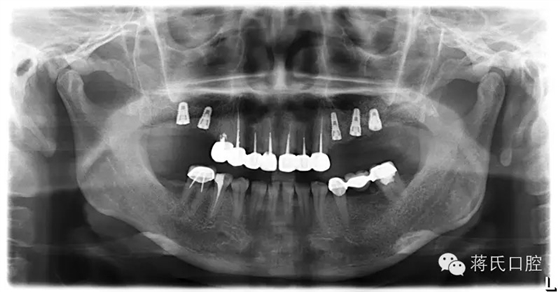

種植前X線,左側(cè)外提升右側(cè)內(nèi)提升

13.種植完成后X

19.修復(fù)完成后X